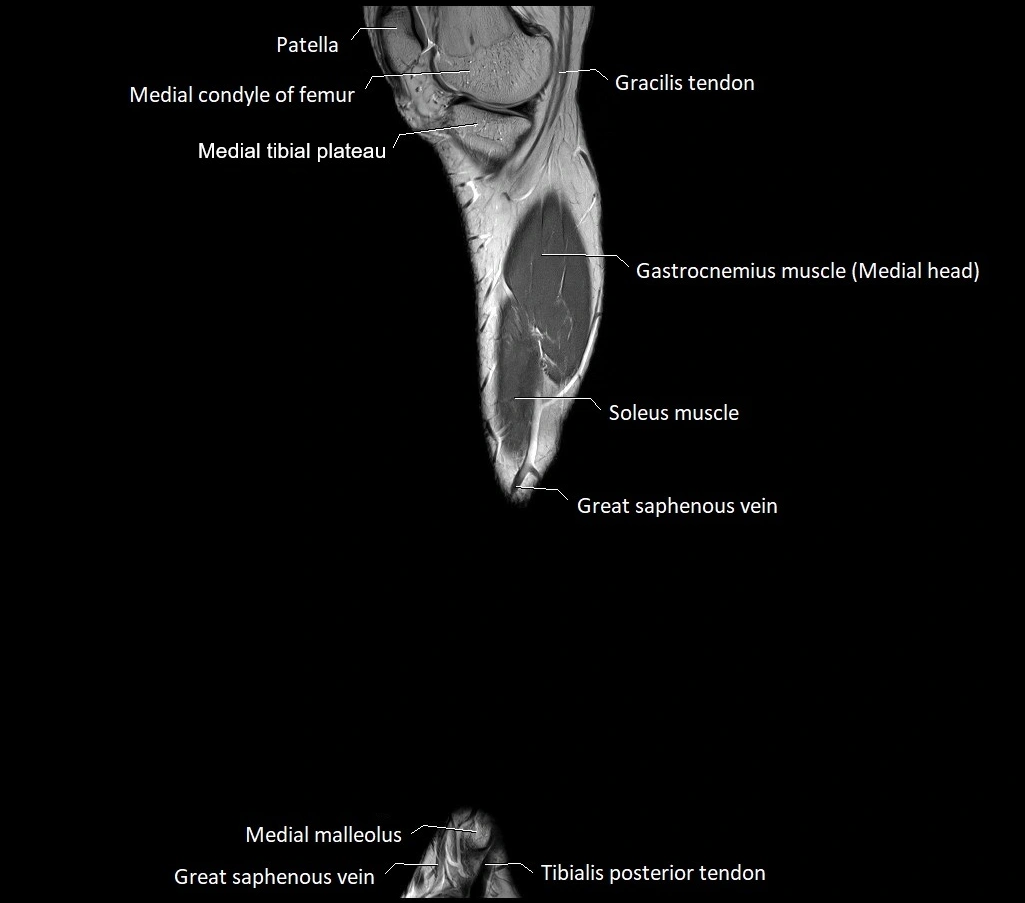

MRI image